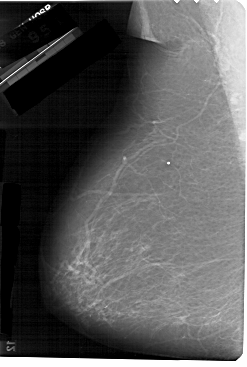

A_1267_1.RIGHT_MLO

RIGHT_MLO LINES 5491 PIXELS_PER_LINE 3121 BITS_PER_PIXEL 12 RESOLUTION 43.5 OVERLAY

FILE: A_1267_1.RIGHT_CC.OVERLAY

TOTAL_ABNORMALITIES 1

ABNORMALITY 1

LESION_TYPE MASS SHAPE OVAL MARGINS CIRCUMSCRIBED

ASSESSMENT 4

SUBTLETY 4

PATHOLOGY BENIGN

TOTAL_OUTLINES 1

BOUNDARY